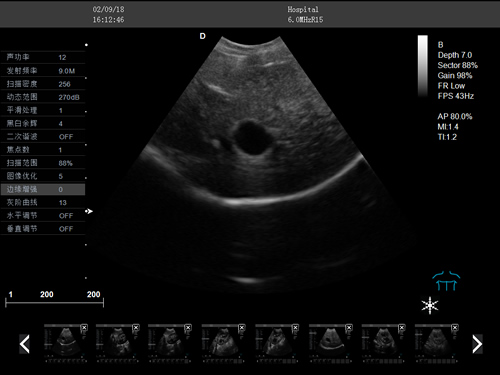

F3-VET推车式兽用彩超机

动物宠物超声诊断仪

彩色多普勒动物超声诊断仪

·支持彩色多普勒、频谱多普勒、能量多普勒等成像技术

·组织谐波成像技术

·中小动物的肝、胆,脾、肾、膀胱、子宫、妊娠等各组织器官的检查和病变的诊断